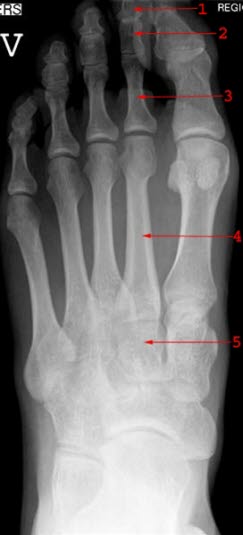

Diagnosen

Normalt røntgenbildeDiagnosen stilles på grunnlag av de typiske funnene. Røntgen kan utelukke leddbetennelse og vise eventuelle slitasjeforandringer i tåens grunnledd. Vanligvis er det unødvendig å ta røntgen for å stille diagnosen, men røntgenbilder er nyttige for kirurgen i forberedelsene til en operasjon.

Stortåen er vridd utover (valgisert) 15-20°. Blir valgusstillingen mer enn 20°, vil trekk i det indre stortåbeinet (grunnfalangen) via bøye- og strekkesener ytterligere forsterke stortåens tendens til skjevstilling (valgisering). Grunnleddet vil bli presset ut og trykk fra sko vil medføre en kronisk irritasjon av en slimpose (bursa) som ligger utenpå grunnleddet. Med tiden vil det dannes en beinet utvekst (eksostose) i grunnleddet, noe som ytterligere forsterker trykkplagene. Stortåens "vandring" vil også påvirke de nærmeste tærne, som kan innta en mer eller mindre uttalt hammertåstilling.